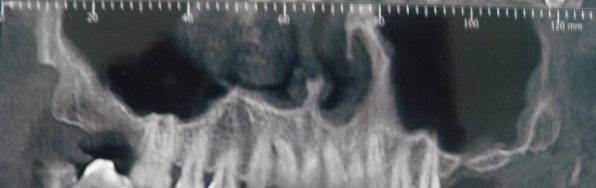

Atrofia diffusa

In conseguenza dell’età nel paziente anziano o talvolta precocemente nel soggetto giovane, si evidenzia atrofia del mascellare superiore spesso accompagnata ad una atrofia anche della mandibola. In tali casi ci si viene a trovare in una grave situazione di III classe scheletrica che per essere corretta richiede l’utilizzo di procedure di chirurgia ortognatica (osteotomia le Fort I). Questa tecnica consente di avanzare il mascellare arretrato e di rialzarlo interponendo tra le linee osteotomiche un frammento osseo prelevato solitamente dalla cresta iliaca. L’innesto osseo viene fissato rigidamente con placche e viti, o in certi casi con gli impianti dentali posizionati immediatamente.

Si possono anche effettuare rialzi dei processi alveolari diffusamente atrofici mediante innesti d’osso definiti onlay fissati alla base ossea mediante viti a compressione o utilizzando gli stessi impianti.

2. Mandibola

Le situazioni di atrofia diffusa della mandibola possono richiedere procedure chirurgiche preimplantologiche molto complesse che vanno dalla distrazione osteogenetica all’apposizione di innesti ossei tipo onlay, talvolta preceduti da interventi di trasposizione e riposizionamento dei nervi alveolari.